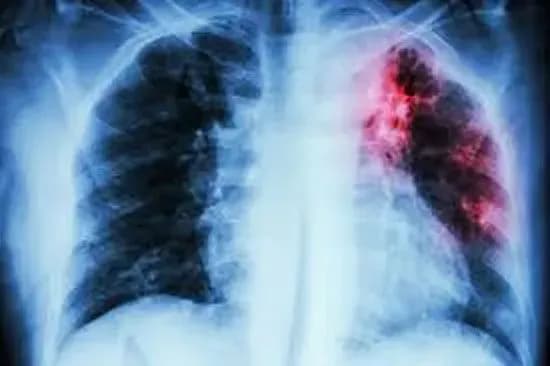

Так, за 9 місяців 2019 року, на обліку в закладах охорони здоров’я перебуває 446 осіб віком від 0-14 років, хворих на всі форми активного туберкульозу.

Додамо, що за відповідний період на обліку в закладах охорони здоров’я перебуває 31 615 хворих на всі форми активного туберкульозу.